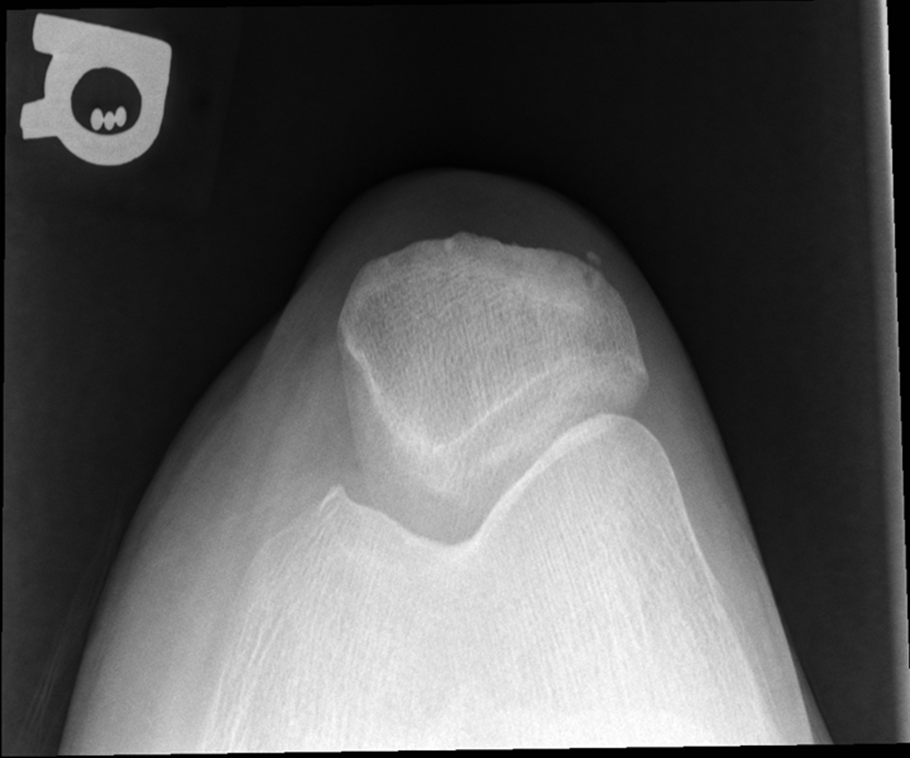

Non Trauma Patella

Erect Settegast method

(Tangential)

•Evidence of proper collimation and the presence of a side marker placed clear of the anatomy of interest

•Patella in profile

•Femoral condyles and intercondylar sulcus

•Open patellofemoral articulation

•Bony trabecular detail and surrounding soft tissues

Tibia is lower under femur underorated!

TOO MUCH TUBE ANGEL OR TOO MUCH LEG FLEXTION, Medial Rotation, larger condyle

Tibia came through joint space, patella is good!!!

Did not flex the knee enough not enough tube angle